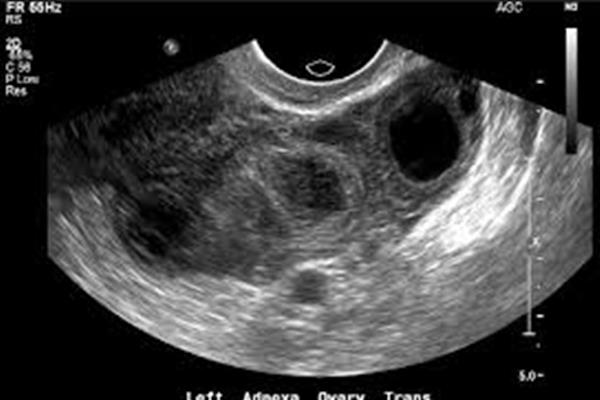

تشخیص دقیق مشکلات و بیماریهای مرتبط با دستگاه تناسلی زنان از طریق سونوگرافی واژینال توسط متخصصان مرکز آوا.

سونوگرافی لگن برای بررسی اندامهای داخلی مانند رحم، تخمدانها و مثانه انجام میشود. در این نوع سونوگرافی، پر بودن مثانه ضروری است و مانند سونوگرافی شکم، توصیه میشود ناشتا باشید و از مصرف غذاهای چرب و نفاخ خودداری کنید.